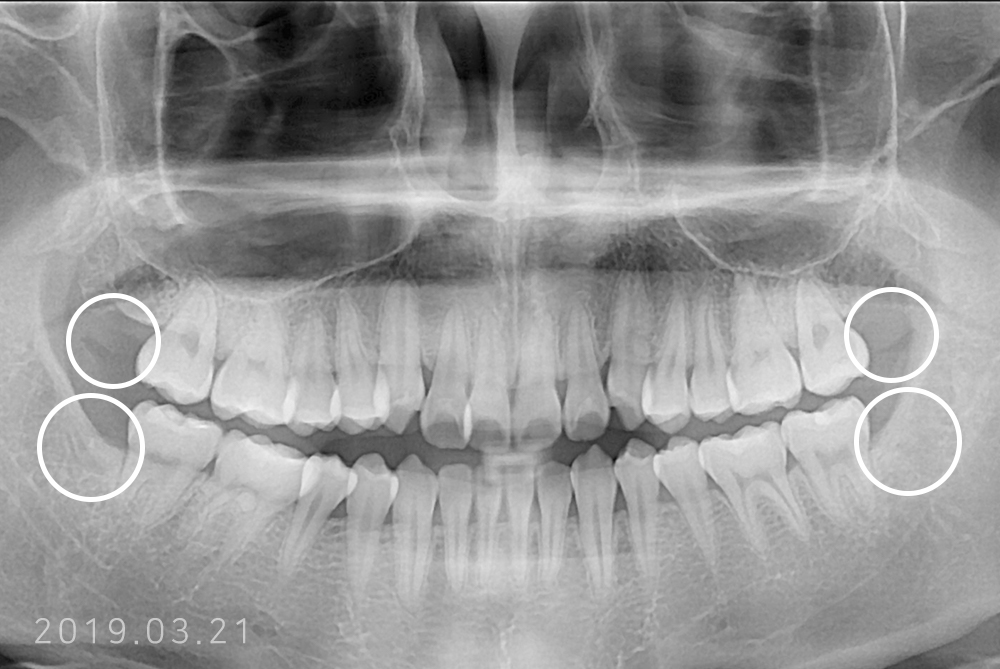

[사랑니] 매복 사랑니 발치

치료후 : 2019-03-21

세종치과는 구강악안면외과학 박사이신 원장님이 발치하는 치과입니다.